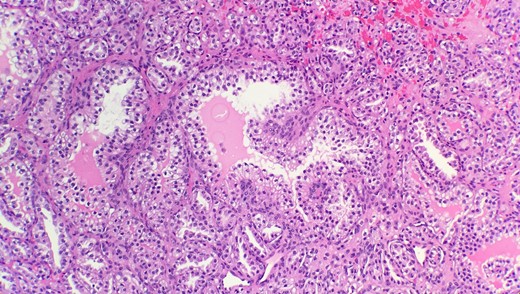

Pathological diagnosis confirmed CCPRCC. Grossly, the partial nephrectomy specimen measured 4 × 3.1 × 2.2 cm. The attached fatty tissue surrounding the kidney measured 10.5 × 7.8 × 2.5 cm. Cut sections showed a tan pink nodule with foci of white tan tissue measuring 3.5 cm. Microscopic examination reveals that the tumor is composed of cystic, tubular, solid and papillary components with clear cells and a low nuclear grade (Fig. 1). Tumor cells were also positive for CK7 (Fig. 2) and negative for CD10 (Fig. 3) and p504s supporting the diagnosis of CCPRCC.

Immunohistochemical stain reveals that tumor cells are negative for CD10 (IHC 40x).